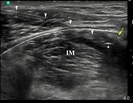

Wobec doświadczeń dotyczących anestezji przewodowej przez igłę, cewniki zakładane pod kontrolą ultrasonografii z dostępu podobojczykowego przedstawiane są jako zapewniające lepszą analgezję, niż te zakładane z dostępu nadobojczykowego. Technika podawania bolusa przez cewnik, która niewątpliwie „sprawdza” skuteczność cewnika przed rozpoczęciem ciągłej infuzji została zbadana dla cewników zakładanych z dostępu podobojczykowego, ale nie dla dostępu nadobojczykowego. Poniższe badanie ocenia technikę podawania bolusów przez cewnik zakładany z dostępu nadobojczykowego i weryfikuje hipotezę, iż cewnik zakładany z dostępu podobojczykowego zapewnia szybszy początek wystąpienia blokady splotu barkowego.